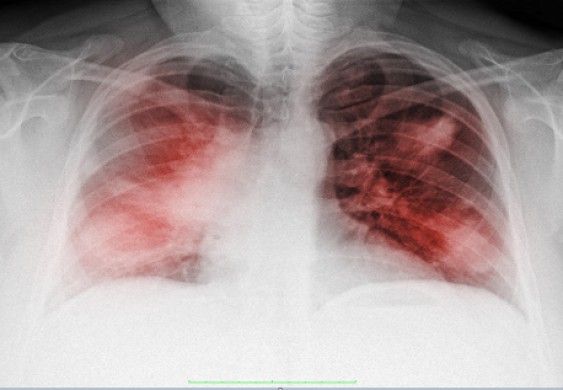

يُعرف نقص الأكسجة الصامت بأنه حالة تثير الغموض لدى الأطباء لتركها المرضى الذين يعانون من كورونا، قادرين على التحدث مع أحبائهم، بينما ينبغي أن يعانوا من أجل استن..